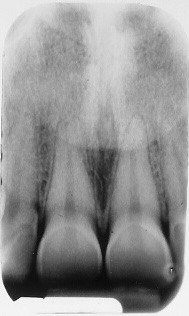

18. What condition can be seen in buccal surface of the teeth # 1.1 ans 2.1?

28. What condition can be seen on buccal surface of the teeth # 1.1 and 2.1?